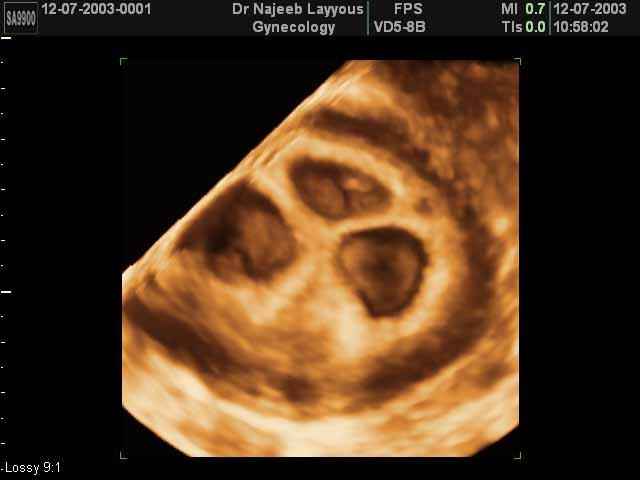

- صور لتوائم

صور لتوائم بجهاز الالتراساوند ثلاثي الأبعاد | الدكتور نجيب ليوس